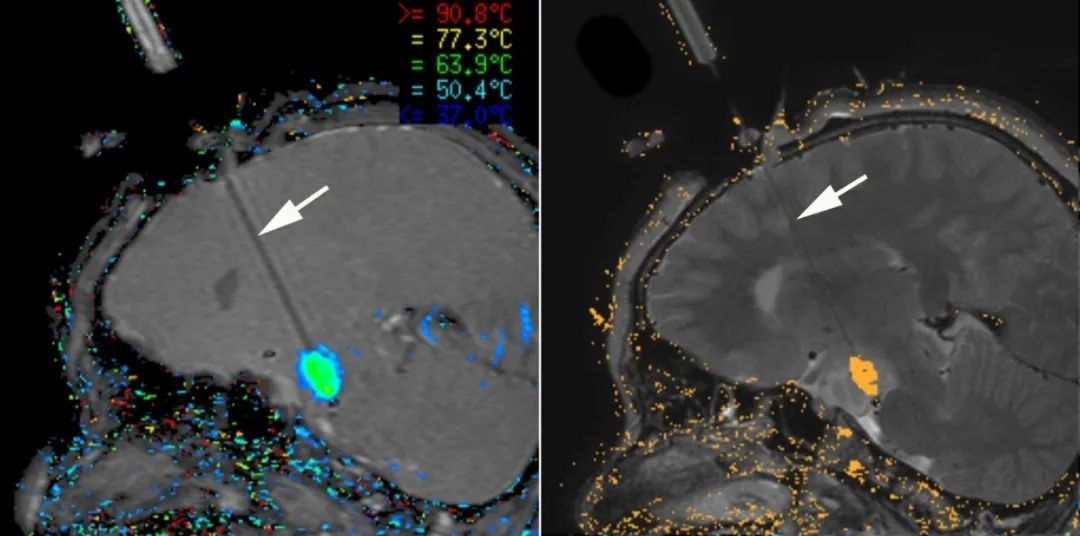

在SickKids,Rutka教授一般使用一种光纤系统在MRI套件中进行激光间质热疗(LITT)治疗。治疗开始之前,Rutka教授一般需要绘制出激光将“瞄准”病灶组织的精确路径,同时还采取了一些技术措施来确保患者的顺利——激光与MRI并用,可以很好地监视大脑的温度,也利于手术团队实时观察沿激光纤维的大脑加热情况,当温度达到约50摄氏度(约122华氏度),只需要几分钟就可以加热并清除脑内病灶,而不用像开颅手术那样需要花费数小时来完成整个手术。